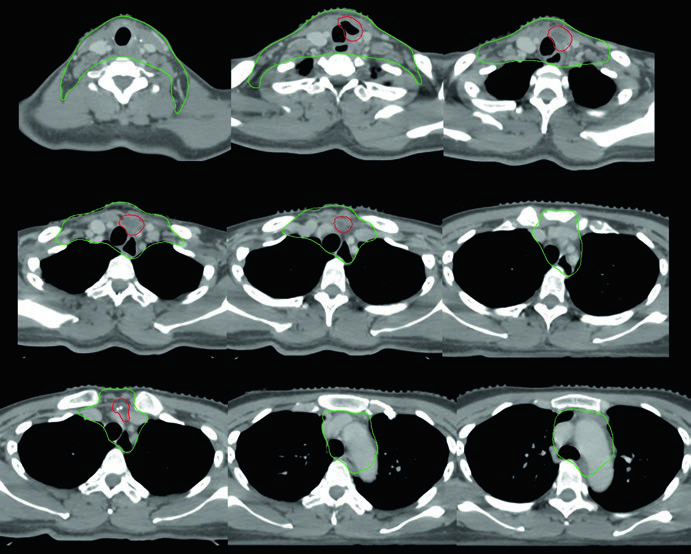

Caso 3 — Anaplásico pós-operatório (Fig. 9.3): Mulher de 50 anos com carcinoma anaplásico submetida a ressecção com extensão extratireoidiana e margens positivas, sem linfonodos envolvidos. Recebeu quimiorradiação pós-operatória. O CTV70 Gy (vermelho) inclui o leito tumoral e os clips cirúrgicos, enquanto o CTV60 Gy (verde) cobre o risco subclínico do compartimento central. A ausência de linfonodos positivos não elimina a necessidade de irradiação subclínica nesse subtipo histológico agressivo — o anaplásico tem taxa de recorrência local e a distância significativamente maior que os diferenciados.

Caso 4 — Recorrência multifocal de variante de células altas (Fig. 9.4): Mulher de 61 anos com variante de células altas do carcinoma papilar, submetida a três cirurgias prévias, que se apresentou com recorrência multifocal. Foi tratada com quimiorradioterapia definitiva. O GTV70 Gy (vermelho) demarca cada foco de recorrência, e o CTV60 Gy (verde) cobre o pescoço subclínico em risco. A variante de células altas é reconhecidamente mais agressiva que a variante papilar clássica, com maior propensão a recorrência e comportamento biologicamente mais adverso.

Quando há recorrência multifocal após múltiplas cirurgias, o campo cirúrgico se torna hostil — fibrose extensa, distorção anatômica e risco aumentado de lesão nervosa tornam nova ressecção proibitivamente arriscada. A quimiorradioterapia definitiva com IMRT permite entregar 70 Gy a cada foco individualmente, com gradiente de dose favorável para os tecidos adjacentes. Cada foco de recorrência exige seu próprio GTV delineado, e o plano precisa acomodar múltiplos alvos de alta dose simultaneamente.